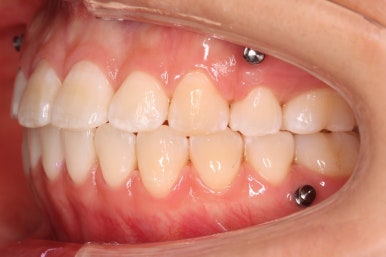

다시 이번 환자분으로 돌아가, 입 안모습을 보시겠습니다.

부산무턱교정 키다리아저씨치과에서 처음 내원하셨을 당시의 입 안의 모습입니다.

아래턱이 작아서 상대적으로 윗니들이 많이 돌출되었고, 뻐드러져 있습니다. 윗니들이 배열되어 있는 형태도 V자에 가깝게 입천장이 좁은 양상입니다.

윗니는 발치를 했고, 잇몸뼈에 미니스크류를 식립하여 앞니를 뒤로 당겨넣고 있습니다.

이 뽑은 틈은 거의 없어져가고 있고, 중간평가 이 후 더 필요한 위치에 미니스크류를 추가하여 당기고 밀고 밀어넣고 다양한 작업을 해주게 됩니다.

중앙선도 잘 맞고 교합도 잘 마무리되었습니다.

중앙선, 교합, 뻐드러짐 모두 좋아졌고 이를 뽑고 교정했지만 발치 공간이 남지 않고 잘 마무리 되었습니다.